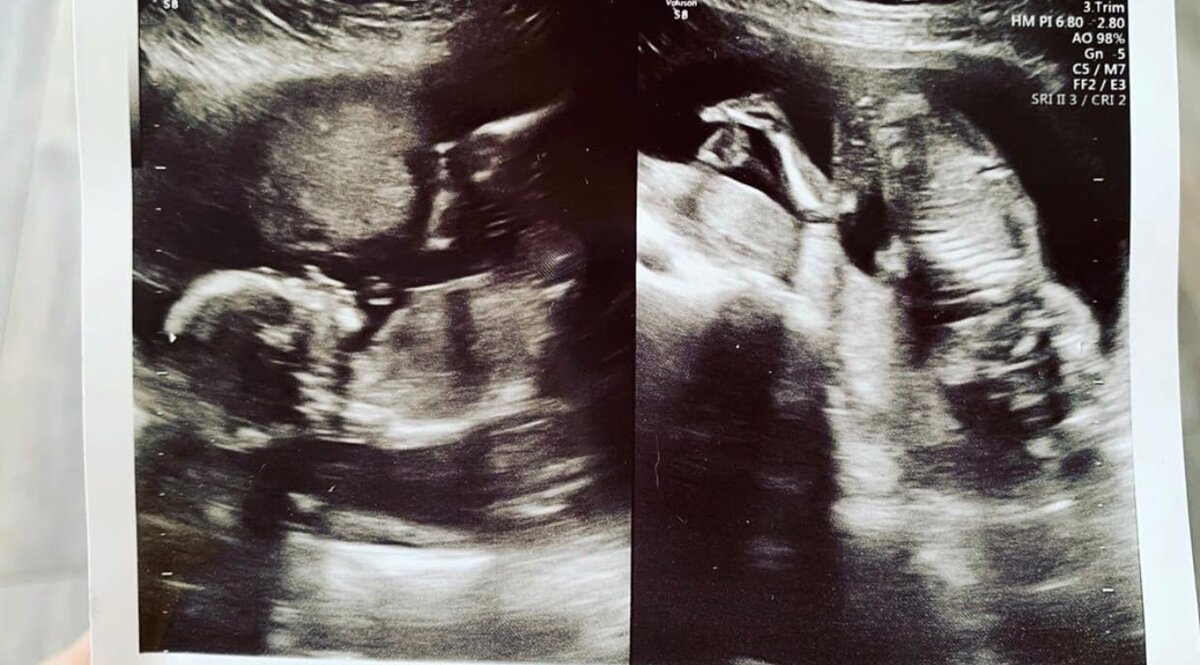

Как родить двойню: мой опыт. Часть 2

Ещё в эту беременность я узнала, что такое «синдром нижней полой вены», и почему беременным не рекомендуют спать на спине) Когда я ложилась на спину, меня начинала охватывать необъяснимая паника, я начинала задыхаться, потом начинало темнеть в глазах. Узнала я это в кабинете УЗИ. Когда я практически «отъехала», врач заметила неладное и перевернула меня на бок) А сама я положение на спине с внезапно накрывающими меня паническими атаками связывать не догадывалась))